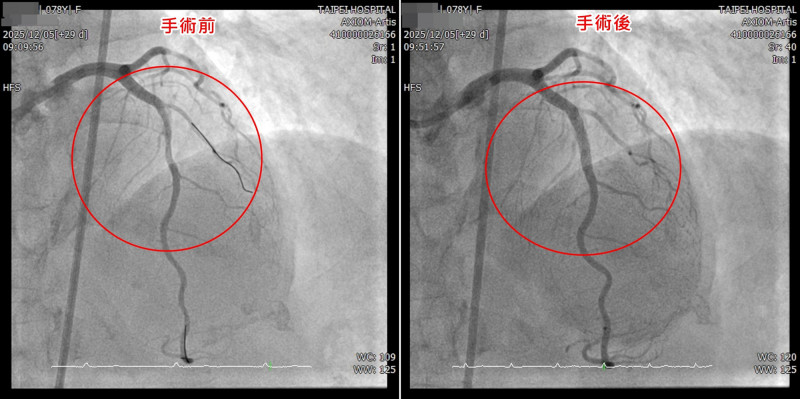

台北醫院表示,1名近80歲的病人近期因胸口不適,檢查發現左前降支的前中段約有80%以上的狹窄病灶,且血管壁存在嚴重鈣化,最狹窄處呈現雙側鈣化,高度疑似環狀型鈣化病灶,屬於傳統氣球擴張成功率低、且血管傷害風險極高的困難病灶,經醫師與病人及家屬說明後,採用血管內震波碎石術,透過高能量震波選擇性擊碎血管壁內鈣化沉積,使血管恢復柔韌度,進而順利完成血管擴張與支架置放,成功完成複雜性高的冠狀動脈介入手術,病人術後恢復情況良好,胸口不適症狀也獲得明顯改善。

台北醫院心臟內科主任黃啟銘說,血管內震波碎石術是革命性的心導管治療方法,醫師透過專屬的球囊導管送入病灶位置,並在低壓下釋放高能量的聲波震動,類似體外碎石治療的概念,能選擇性擊碎血管壁內堅硬的鈣化沉積,讓原本如石頭般堅硬的血管重新變得柔韌,進而安全地完成氣球擴張與支架置放,最大特點在於「精準、低壓、安全」,只針對鈣化病灶發揮作用,避免對正常血管組織造成過度傷害,讓治療變得更為可行與穩定。